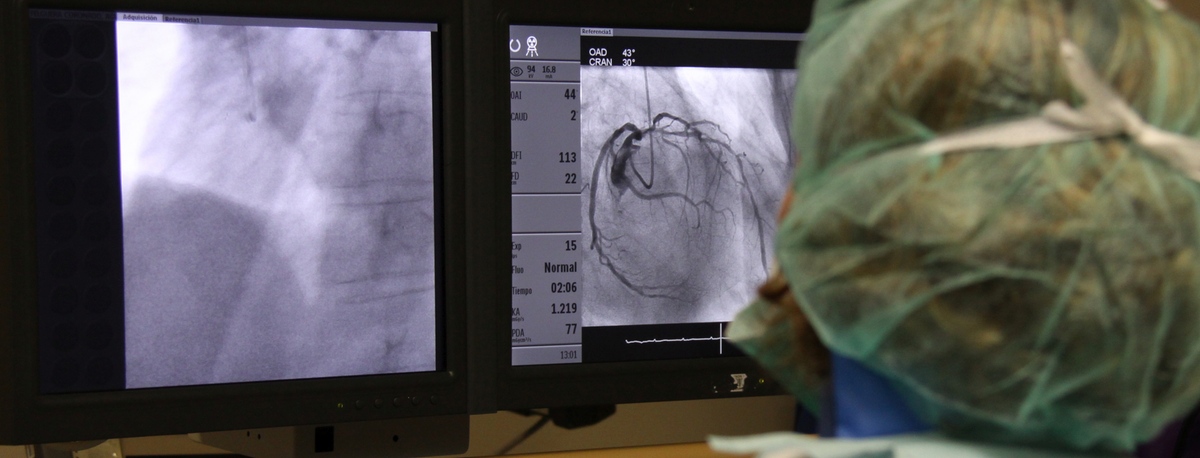

Instituto del Corazón Quirónsalud Teknon

Treatments and Specialities

The institute is staffed with specialists in angiology, vascular surgery, and endovascular surgery, who handle everything from diagnosing to monitoring circulatory system illnesses.Cerebral embolism and pulmonary thromboembolism are some of the leading causes of death due to vascular problems.

Our team specialises in minimally invasive techniques, using endovascular techniques without surgery, which allow vascular prostheses to be implanted to resolve dilations or aneurysms of the arteries. We also offer all treatments for venous and peripheral arterial disease, including carotid artery disease.